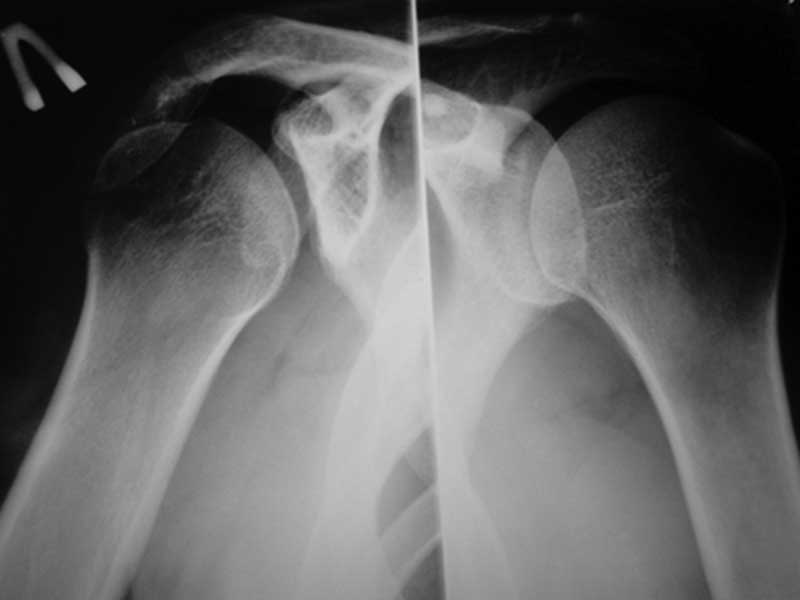

Уважаемые коллеги! Требуется ваша помощь. На консультацию обратился пациент 30 лет с

жалобами на ограничение активных движений в левом плечевом суставе.

Пассивные в полном объеме. Со слов имела место некая родовая травма. К тому же отмечается незначительный

дефицит иннервации n.radialis (снижение ╚ силы ╩ разгибателей-сгибателей в кистевом

суставе и отведения 1 пальца; неврологи никакого специфичного лечения не назначают). Также

имеется контрактура локтевого сустава: сгибание в полном объеме, разгибание 150 градусов,

супинация в пределах 7 градусов. Функция конечности в принципе устраивает. Скелетных травм

в анамнезе нет. Вопрос: есть ли смысл заниматься какими-либо реконструкциям на плечевом

суставе и как можно улучшить функцию скомпрометированных суставов? Заранее всем

благодарен